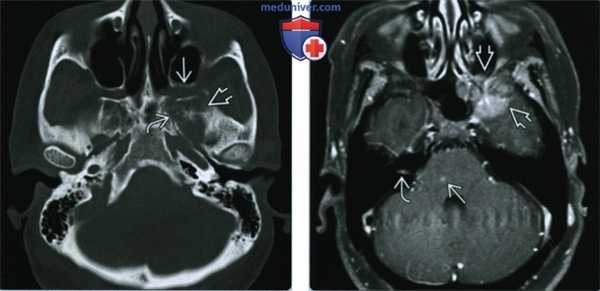

(Слева) При аксиальной КТ в костном окне у пациента, страдающего раком легких, с жалобами на боли в области лица слева и головокружение определяется литическое новообразование левой половины тела клиновидной кости. Обратите внимание на эрозию видиева канала, неровность краев крылонебной ямки и инвазию мягких тканей.

(Справа) При МРТ Т1 FS c КУ b аксиальной проекции определяется контрастное объемное образование крыла клиновидной кости, прорастающее в твердую мозговую оболочку. При более внимательном рассмотрении обнаружены лептоменингеальная опухоль в правом внутреннем слуховом проходе и мелкий метастаз в мост.